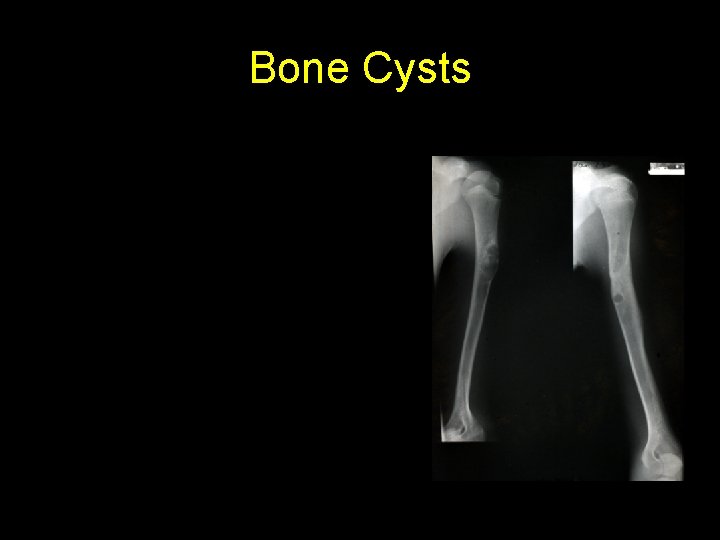

Bone Cysts simple bone cyst l fibrous dysplasia l aneurysmal bone cyst l

Simple bone cyst • Unicameral bone cyst • Metaphysis of long bones (humerus , femur) • Centric • Filled with straw-coloured fluid

• Bone Cyst – A wall of fibrous tissue filled with clear fluid • Clinical presentation • Pain • Not diagnosed unless a pathological fracture occurs.